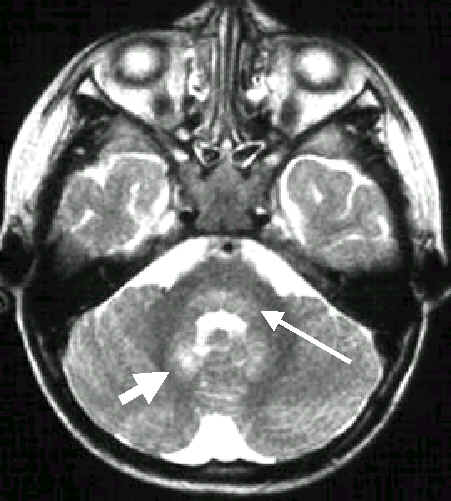

腦炎侵犯

橋腦的後及腦齒狀核

橋腦的後面

(細長箭)

及小腦齒狀核(粗短箭)